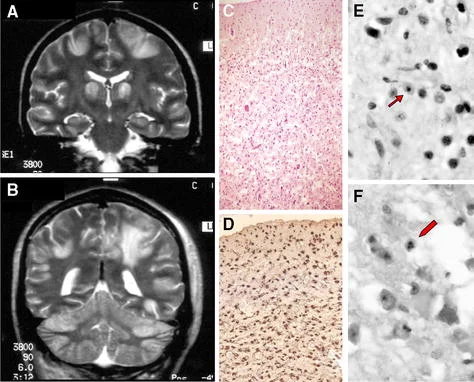

بیماری آلپرز معمولا در اوایل دوران کودکی شروع میشود و معمولاً با تشنج در هر سنی بین 3 ماهگی تا 5 سالگی نشان داده میشود. این بیماری با عدم هماهنگی حرکات، فلج جزئی، تشنج و انقباض عضلانی مشخص میشود. کودک قادر به دستیابی به تون ماهیچه طبیعی (هیپوتونی یا hypotonia) نیست، با این حال به نظر میرسد اندامها سفت هستند. در معاینه MRI افزایش تراکم ماده خاکستری در مغز مشاهده میشود. معمولا اما نه همیشه، بیماری آلپرز با آسیب کبدی همراه است.

سندرم آلپرز معمولاً در دوران نوزادی بر اساس ارزیابی بالینی کامل، شرح حال دقیق بیمار و انواع آزمایشات تخصصی تشخیص داده میشود. چنین آزمایشاتی ممکن است شامل مطالعات تصویر برداری تخصصی از مغز باشد که ممکن است انحطاط بخش خارجی (قشر مغز یا cerebral cortex) و در برخی موارد، سایر نواحی مغز را نشان دهد.

الکتروانسفالوگرافی (Electroencephalography یا EEG) که تکانههای الکتریکی مغز را ثبت میکند، ممکن است کاهش کلی فعالیت الکتریکی مغز و یا سایر ناهنجاریهای تخلیه الکتریکی مشخصه فعالیت تشنج را نشان دهد. تنها تایید پس از مرگ با بیوپسی مغز امکان پذیر است.